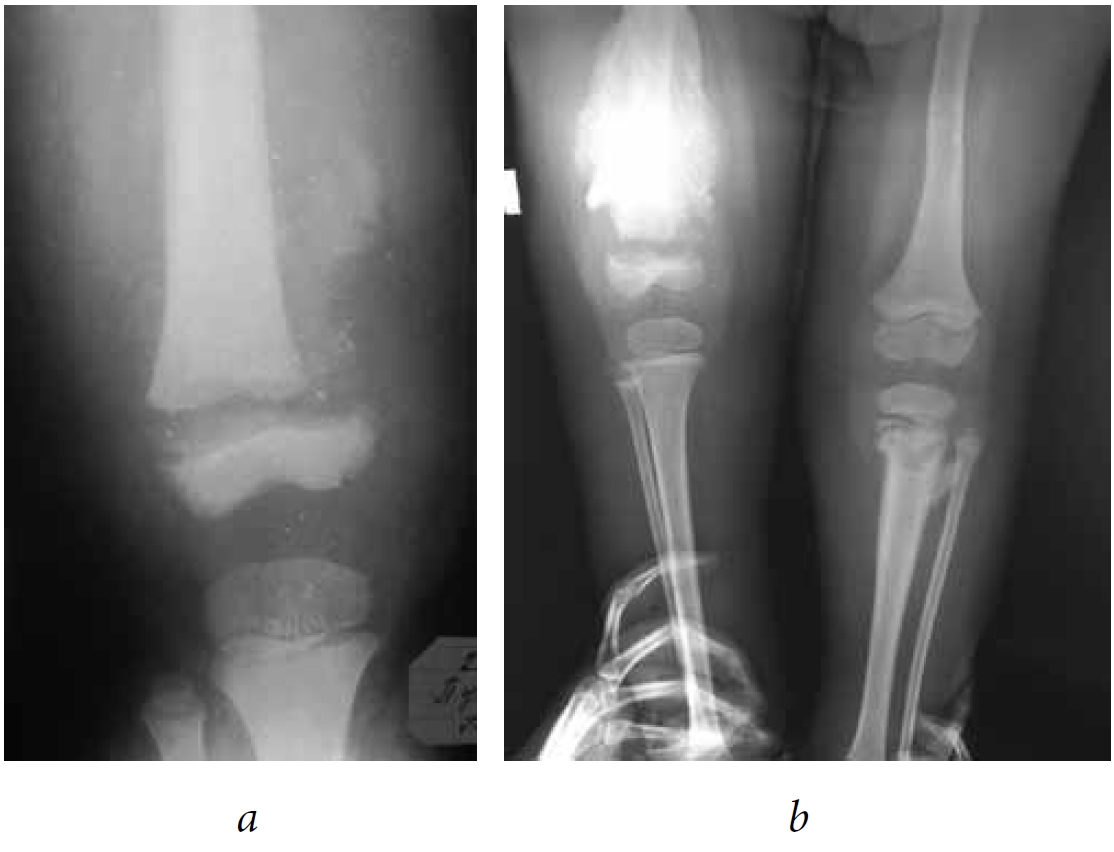

The radiological features of an atypical fracture of long tubular bones in pediatric patients with the consequences of spina bifidas include the absence of a fracture line, the presence of an excess periosteal reaction, and sclerosis at the fracture site (Fig. 2).

Fig. 2. Patient G. The diagnosis is the consequence of spina bifida. Neurosegmental level L1–L2. Osteoepiphysiolysis of the distal femoral epiphysis on the right: a — day 14 after injury; b —week 5 after injury, hypertrophic periosteal reaction

Hypertrophic callus was detected in 31 of 134 (23%) patients. In a retrospective analysis, it was revealed that the atypical nature of the X-ray pattern of the fracture in 10 patients required a bone biopsy to rule out osteogenic sarcoma, and in five patients, the excess callus was mistakenly interpreted as a manifestation of osteomyelitis. Knowledge of the radiological aspects of atypical fractures of the long tubular bones in patients with the consequences of spina bifidas enables us to conduct a correct differential diagnosis and develop appropriate treatment tactics.